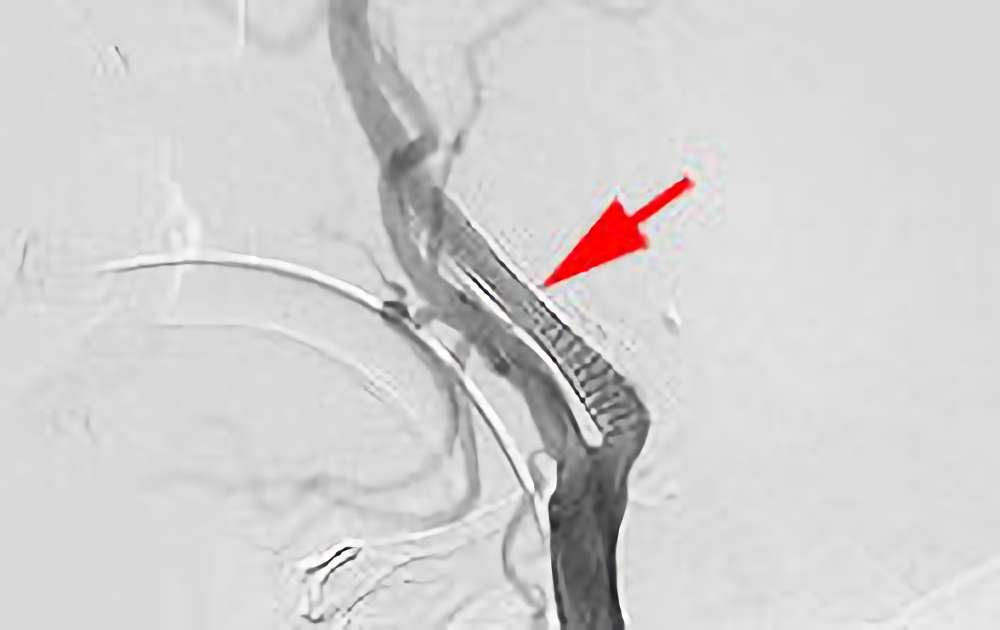

859

'20年7月20日

右内頚動脈狭窄症

70代

大阪府の病院

手術写真

治療

前

中

後

手術日